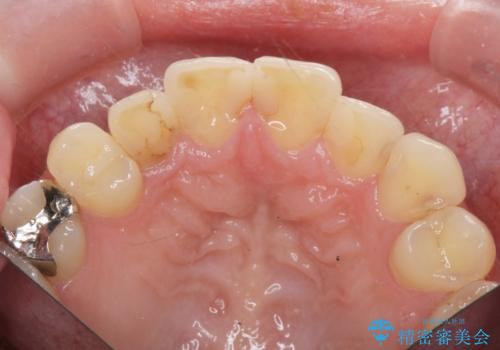

- 神経をとった前歯の変色や、前歯の充填物の変色が大きくなってきたので審美性の改善を求めて来院されました。

充填物や充填物下に再発した虫歯を丁寧に除去し、セラミッククラウンによる審美性の改善、虫歯治療を計画します。